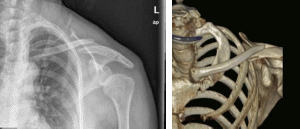

▲术前影像提示左锁骨中段斜行骨折

手术当天,在林世磅主任的指导和规划下,由创伤骨科黄复铭主治医师主刀,运用天玑骨科手术机器人为患者梁姨成功进行了骨科机器人辅助下左锁骨骨折闭合复位弹性髓内钉内固定术。术后X光提示骨折复位满意,固定牢靠,手术切口仅1cm小切口,几乎“隐形”,术后五天患者各项功能即恢复良好。